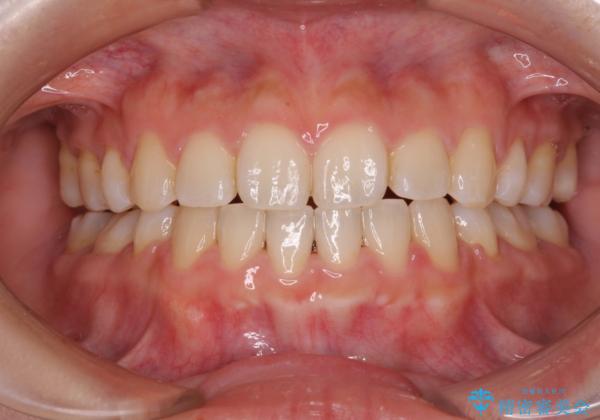

口が閉じられない ワイヤー装置による矯正治療

- 前歯が突出しているために口が閉じられないとのことで来院された患者様です。

上下ともに顎が小さく、歯列が前方に突き出していたため、上下左右の第一小臼歯4本を抜歯し、口元の突出感を改善していくこととしました。

口元の突出感が改善されると睡眠中の口呼吸が予防でき、鼻炎などの疾患予防に繋がると言われています。